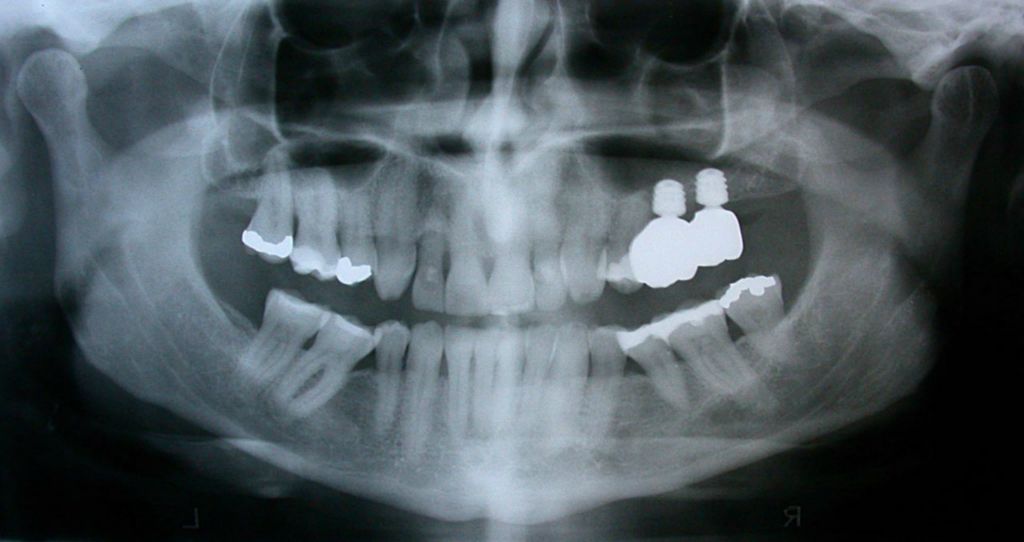

Before